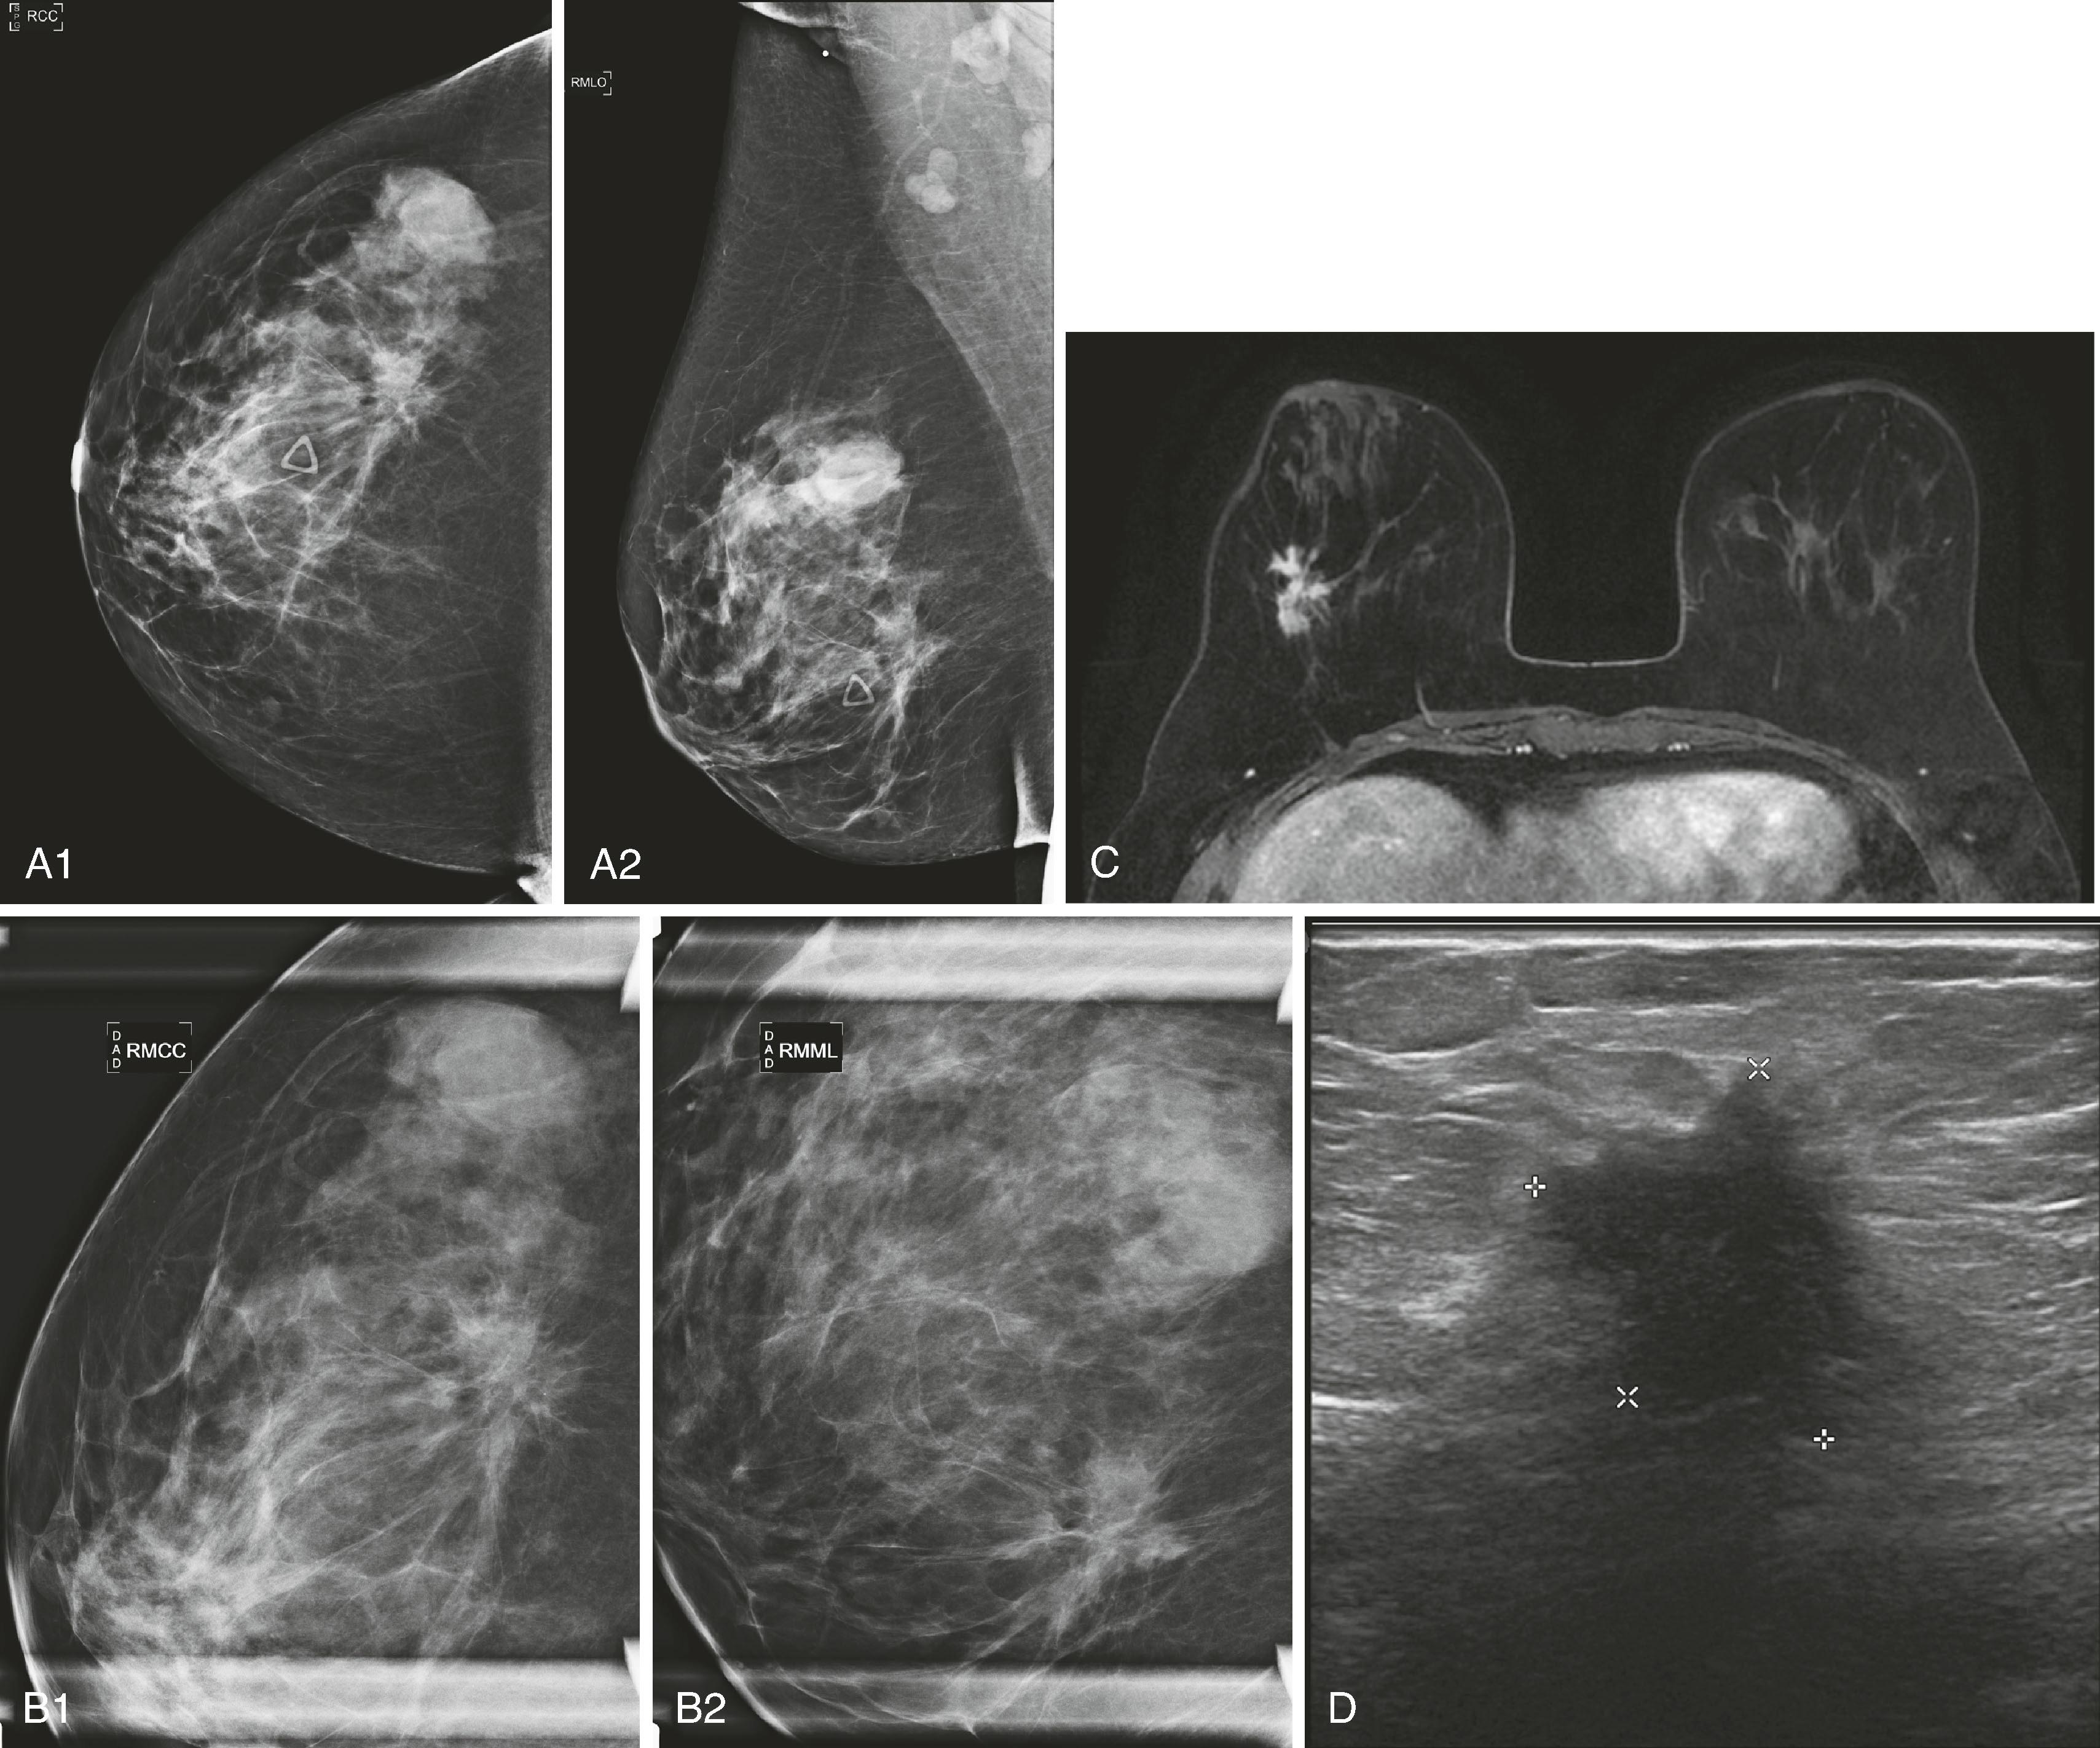

Sonographic features of benign masses, originally reported by Stavros and coworkers, include three or fewer gentle lobulations, orientation parallel to the chest wall, and a thin echogenic pseudocapsule, along with absence of any malignant features. Other features favoring a benign etiology are oval shape, circumscribed borders, and uniform hyperechogenicity ( Fig. 8.15 ). However, many benign-appearing masses undergo percutaneous or excisional biopsy because they are new or enlarging and cannot be unequivocally distinguished from well-circumscribed malignancies ( Fig. 8.16 ). A very large but well-defined mass is suspect for a phyllodes tumor ( Fig. 8.17 ).

Fig. 8.15, A fibroadenoma typically has well-defined margins and an oval shape with three or fewer gentle lobulations.

Fig. 8.16, This 4.5-cm palpable mass has well-defined margins on Right Mediolateral Oblique view (RMLO) on mammography ( A ), but on sonography ( B ), it has inhomogeneous internal echoes and a few microlobulations. Biopsy revealed infiltrating duct carcinoma, nuclear grade 3.

Fig. 8.17, This 3.4-cm palpable malignant phyllodes tumor has circumscribed margins. Pathology revealed mild to moderate pleomorphism, with six mitoses per 10 high-power fields.